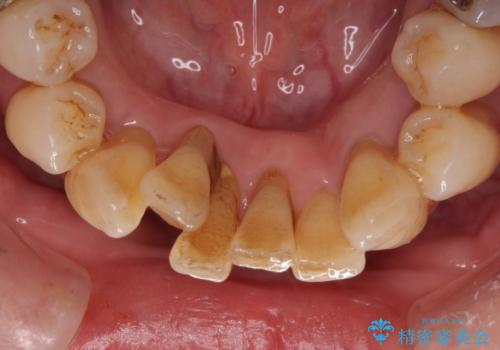

歯周病でグラグラの歯 矯正治療と歯周外科を併用した総合歯科治療

診察を行ったところ、重度歯周病の状態の上に上下の歯列が著しい叢生という状態でした。

歯周初期治療として抜歯や歯槽骨再生治療を行い、さらに歯周ポケット除去を行った後に矯正治療で歯列を整えて行くこととしました。